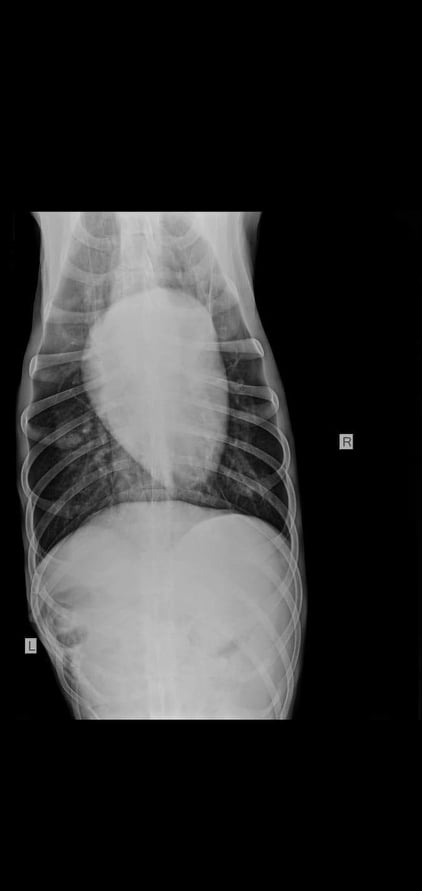

Sancho hat eine alte Verletzung, die ihn jedoch nicht beeinträchtigt: Alte Rippenbrüche… wie dies passiert ist, ist unbekannt.